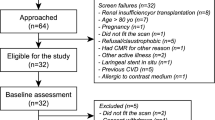

This observational retrospective study includes 54 consecutive patients with biopsy-proven ECD referred to our Institution (IRCCS San Raffaele Hospital, Milan, Italy) between June 2009 and December 2021.

In the present study we included all patients with clinical suspicion of cardiac involvement at multimodality evaluation (clinical evaluation, laboratory test, electrocardiogram, and echocardiography) who underwent CMR for disease confirmation and characterization before therapy start (Fig. 1). Only 29 of 54 patients met this inclusion criteria and were included in the present study. The study was approved by the Ethic Committee and all patients signed informed consent.